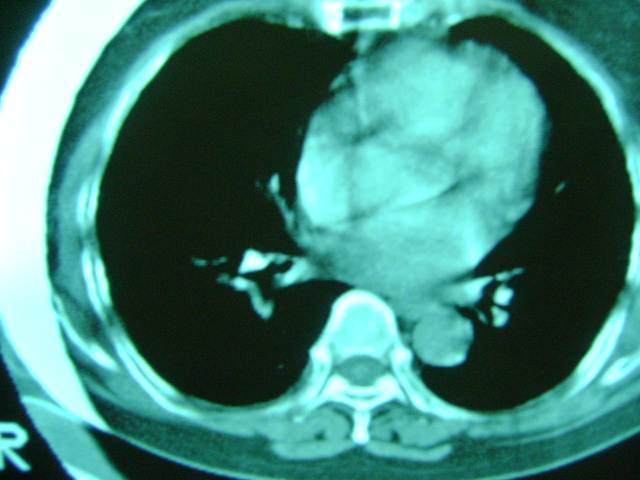

朋友的母亲,56y,咳嗽三个月,感觉左肺门不对,请大家给点意见

心功能不全肺淤血

老年人,肺动脉略迂曲

肺内应该存在感染